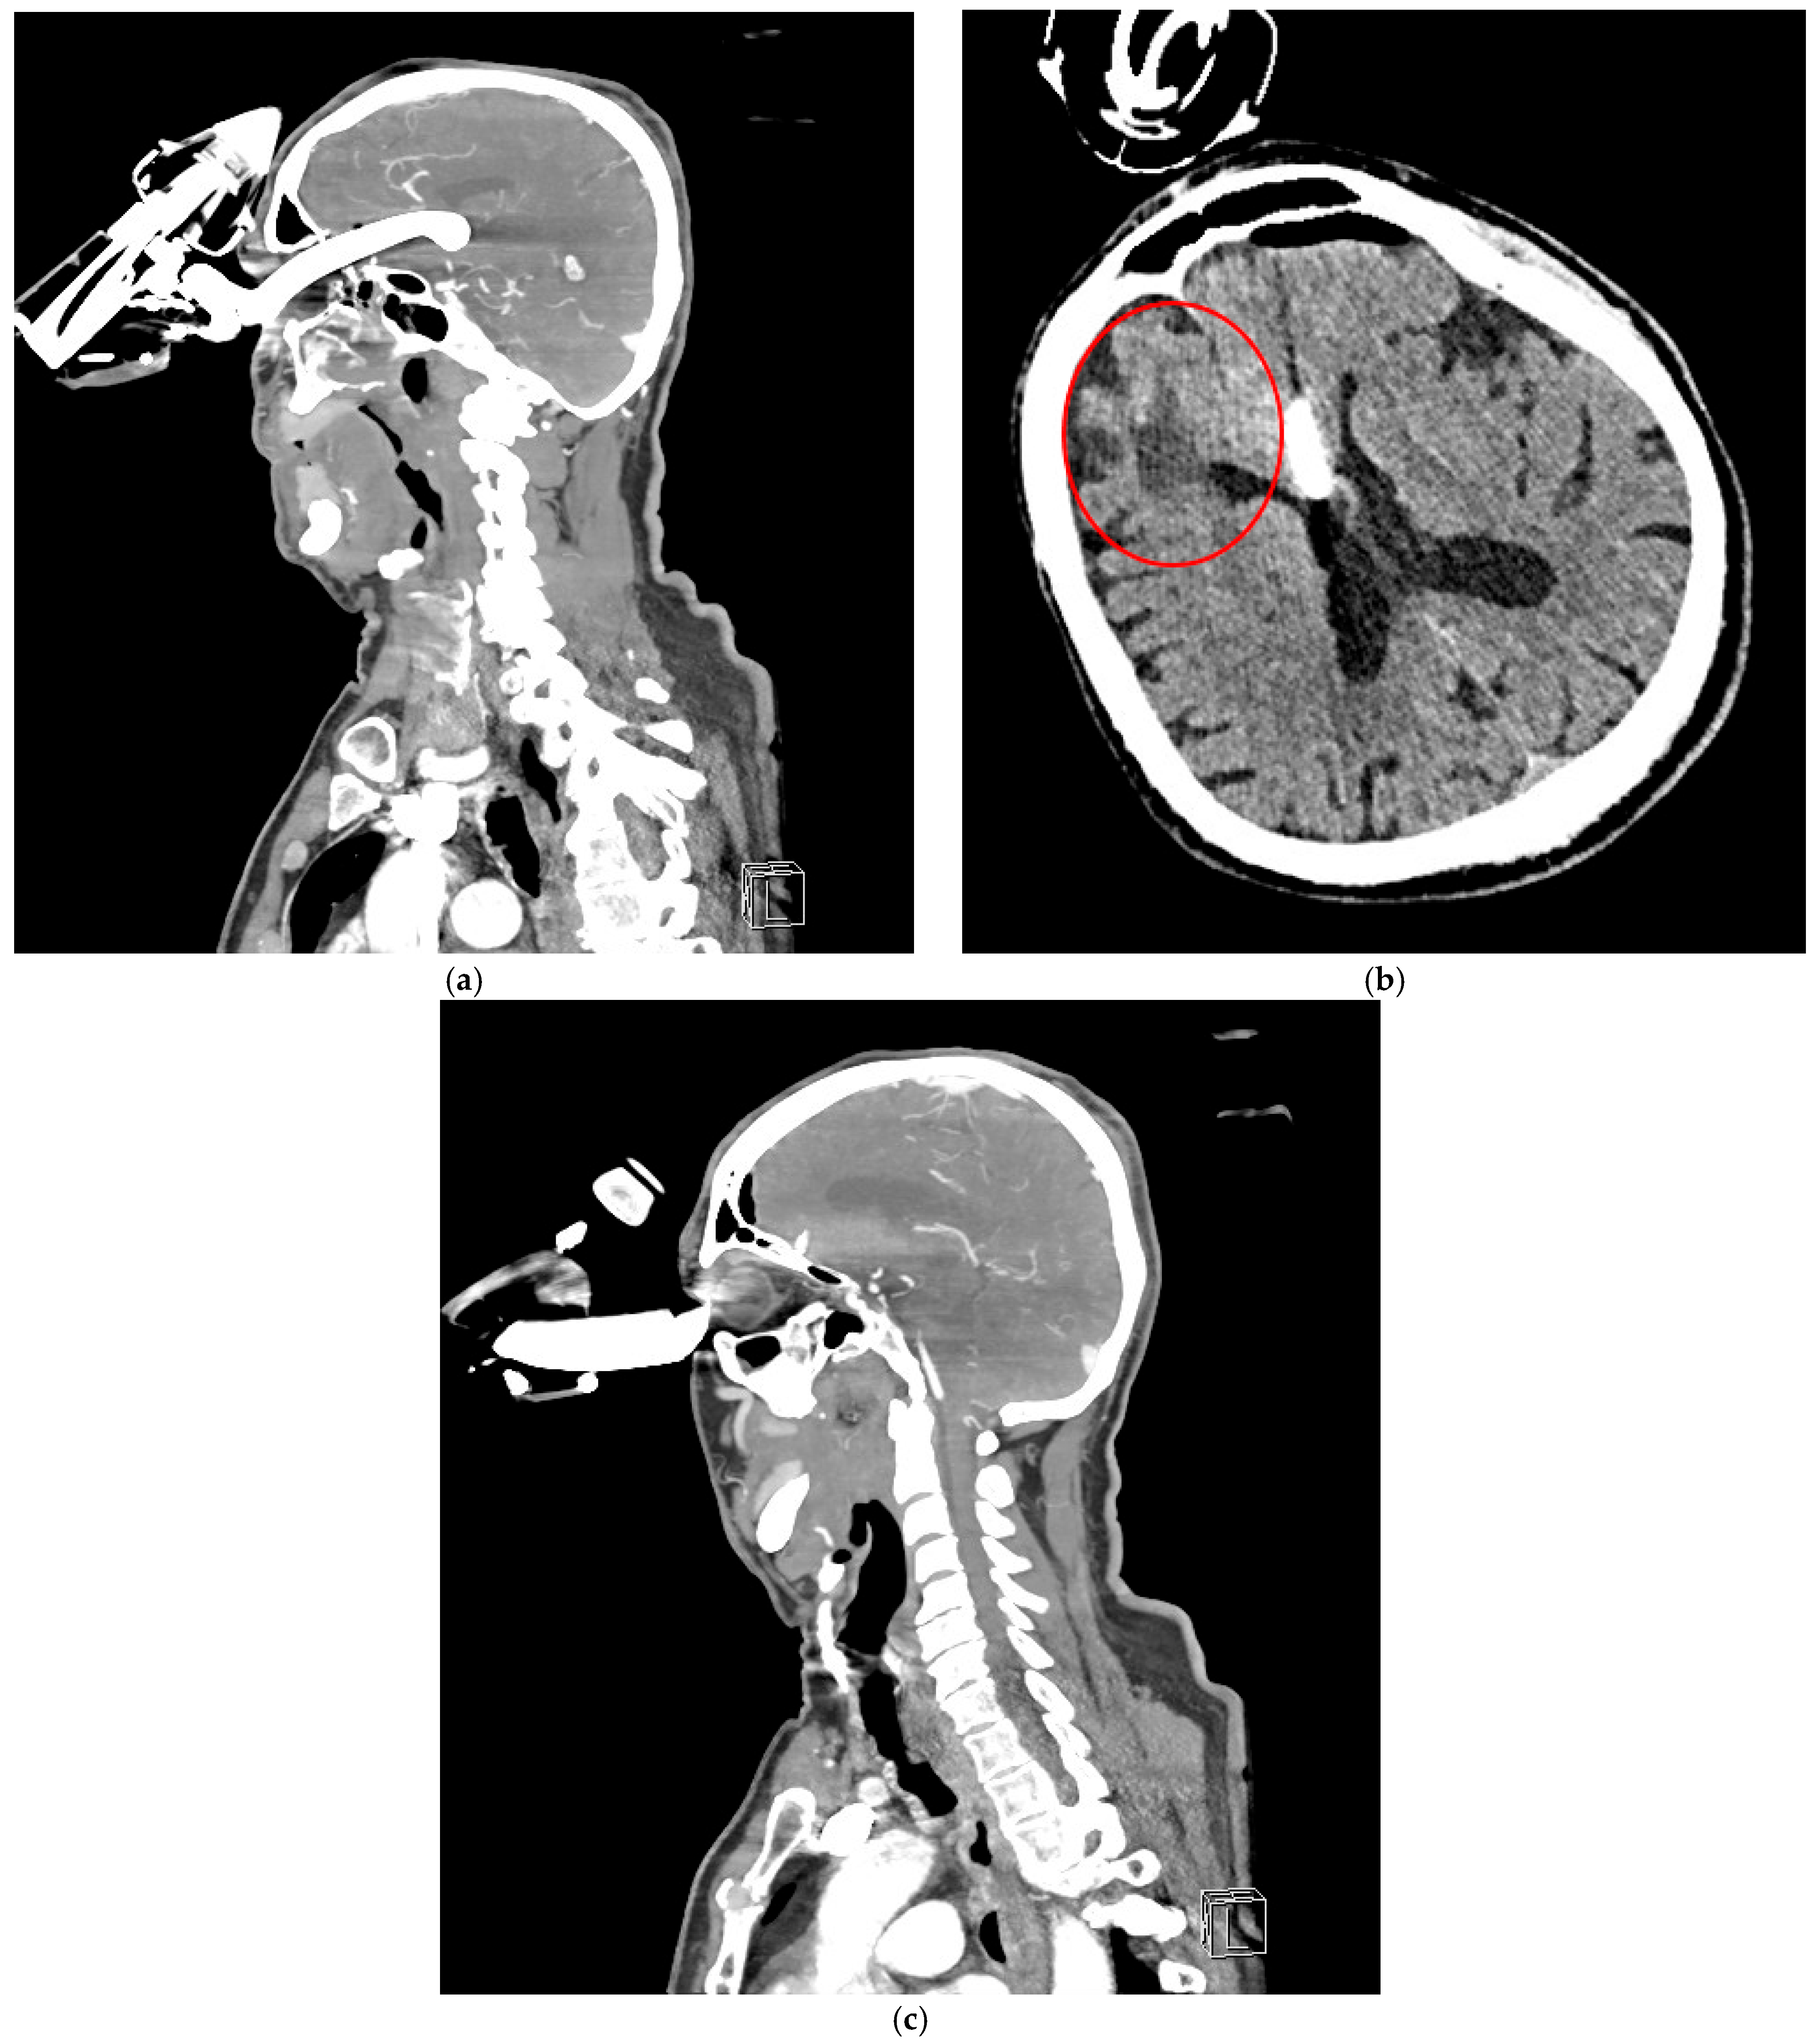

Figure 3. CTA revealed a foreign body penetrating the left orbit into the anterior cranial fossa, extending into the third ventricle to a depth of approximately 64 mm (a). The anterior cerebral arteries were visualized along the foreign body, both running on its left side. No significant intracranial hemorrhage was observed. Additionally, features of porencephaly were noted, likely resulting from a previous injury to the right frontal lobe (red circle—the patient had a history of two head CT scans at our hospital, in 2012 and 2014, which showed evidence of porencephaly) (b). The ventricular system was normal in size and position, without displacement or enlargement. (c) The left eyeball was displaced laterally and inferiorly, compressed by the foreign body, but showed no evidence of direct injury.